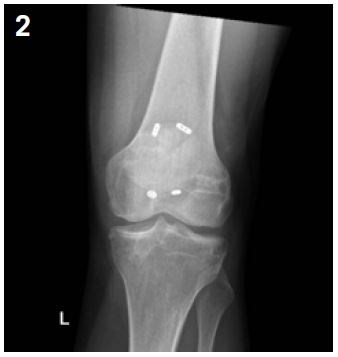

Superior cortex fractures are particularly at risk of displacement so simple fixation by percutaneous screwing can be considered. Generally, three 6.5 mm diameter cancellous screws are placed under fluoroscopic control. In more advanced cases or in heavier or overweight patients, a more sturdy fixation such as a dynamic hip screw may be proposed14 (Figures 2 and 3).

Patella stress fracture: 1% of all BSF20. It mainly occurs in young female athletes (3 women to 2 men). Risk factors are patellar malalignment and lateral tracking dysfunction21.

Clinically, patients present with anterior knee pain associated with sport, sometimes with an associated joint effusion. Patellar palpation is painful12.

XR sensitivity is low.  MRI is more specific and enables an accurate diagnosis and can identify any associated lesions (such as a cartilage lesion).

Treatment is not always surgical. Incomplete and non-displaced fractures may benefit from a 6-week period of immobilization without weight bearing. But if the fracture is displaced and in high demand patients, surgical fixation can be performed with two non-absorbable braided wire devices secured by a button at each end (such as Syndedsmosis TightRope or Invisknot ankle syndesmosis) with efficient stabilization while avoiding the disadvantages of metallic devices that will have to be removed. Return to sports activity can be expected at six months post-op6 (Figures 4 and 5).